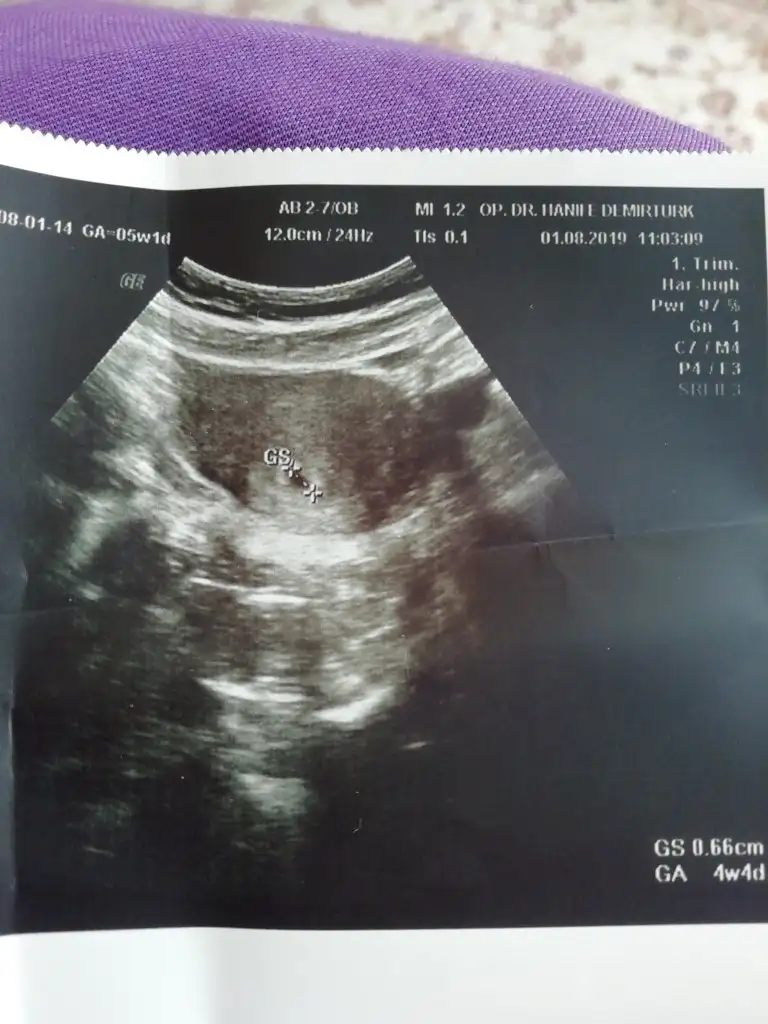

Normal canım daha geriden gelen bebekler bile yakalıyor günlerini hayırlı olsun inşallah ben de görürüm en kısa zamandaMerhaba kızlar bugun keseyı gördüm doktor 4+4 dedı adet tarihine göre ama 5+1 heralde normal bakın bızım mınık burda

Merhaba kızlar bugun keseyı gördüm doktor 4+4 dedı adet tarihine göre ama 5+1 heralde normal bakın bızım mınık burda

aa çok sevindim canım sağlıkla büyüsün inşallah ultrason kağıdında 5+1 yazıyor neden 4+4 dediMerhaba kızlar bugun keseyı gördüm doktor 4+4 dedı adet tarihine göre ama 5+1 heralde normal bakın bızım mınık burda

Sanırım adet tarihine göre öyle yazdı bilmem 4+4 dedı sag ol canm amınaa çok sevindim canım sağlıkla büyüsün inşallah ultrason kağıdında 5+1 yazıyor neden 4+4 dedi